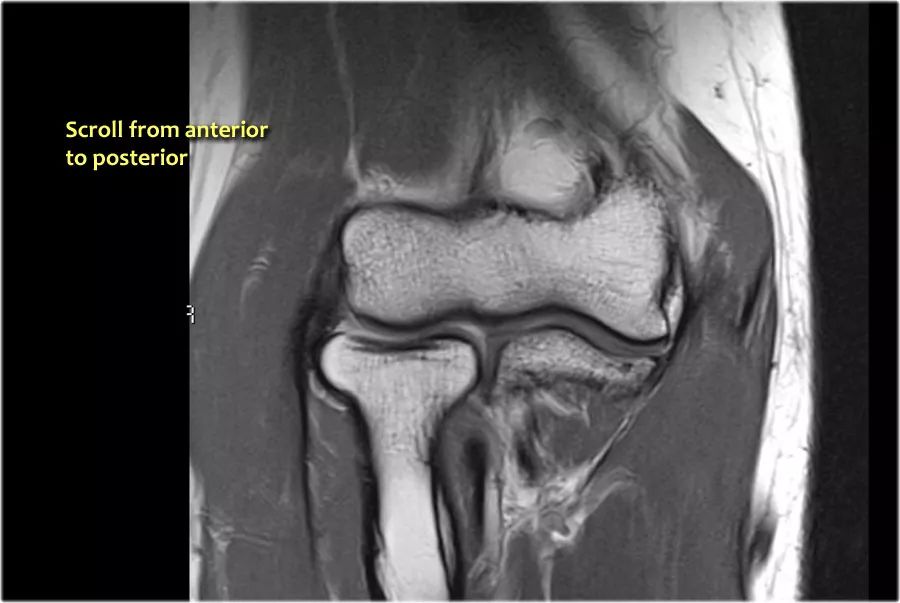

尺神经:在这里,我们看到了肘管内的尺神经。尺骨侧支带的后带形成隧道的底部,而支持带形成屋顶。

该患者有尺神经神经病变。肘管综合征是一种常见的周围神经病变。它产生于肘管内尺神经,其中该神经传递肘管支持带的下方的压缩。

肘管综合征的可能原因● 过度使用● 由于纤维组织中的先天性松弛,尺神经半脱位● 肱骨骨折伴游离体或愈伤组织形成● 由上髁或鹰嘴引起的关节炎● 存在肌肉异常● 软组织肿块:神经节,脂肪瘤,骨软骨瘤,继发于类风湿性关节炎的滑膜炎,感染(例如结核病)和出血。

当他们将尺神经带出隧道时,他们把它放在哪里,它可以是皮下,肌肉下或肌肉内。

因此,当我们回到图像时,您会发现很难找到神经。任何这些皮下结构都可以是转位神经。一种方法是远端跟随结构,直到你发现远端的尺神经位于由脂肪包围的前臂近端的正常位置。然后当你向近端跟随它时,你会发现这是皮下移位。

在这种情况下,有神经炎。神经增大。在T2W图像上有高信号。另一个标志是在矢状图像(箭头)上看到的束的不均匀扩大。